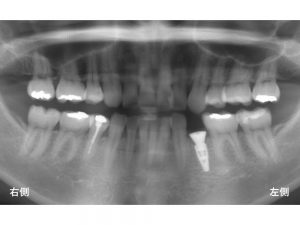

初診のレントゲンが以下です。

下顎の左側奥から3番目の歯が折れてしまっているため、抜歯が必要な状態でした。

以下の赤丸です。